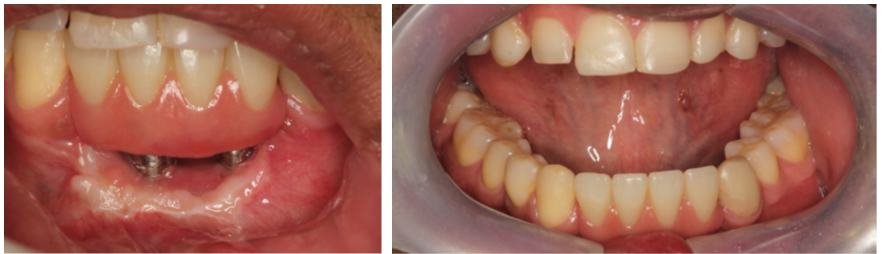

Após três meses, foi realizado enxerto gengival livre e o aprofundamento de vestíbulo.

Na sequência de imagens, podemos perceber a formação de gengiva inserida e a devolução do vestíbulo que tinha sido totalmente perdido.